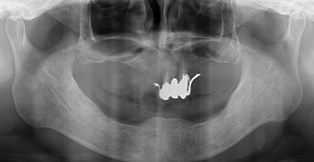

今日の患者さまは当院に来院した時点ですでに下アゴには歯が1本もなく、上アゴには2本の歯を土台としたグラグラしたブリッジがあり、入れ歯を上下に入れておられましたがかなり食事や会話に苦労されていました。

残念ながら上アゴの歯は歯を残したとしても返ってその部分を支点にして入れ歯が動いてしまい、あまりいい結果をだせないので抜かせて頂きました。今日はまずは下顎に4本のインプラントを植えさせていただきました。